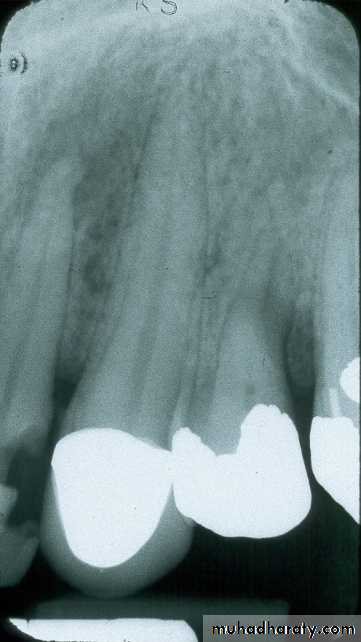

Maxillary Molar

film centered on second molarfilm in center of palate

film equidistant from palatal surfaces of teeth (red arrows); this opens contacts between the teeth.